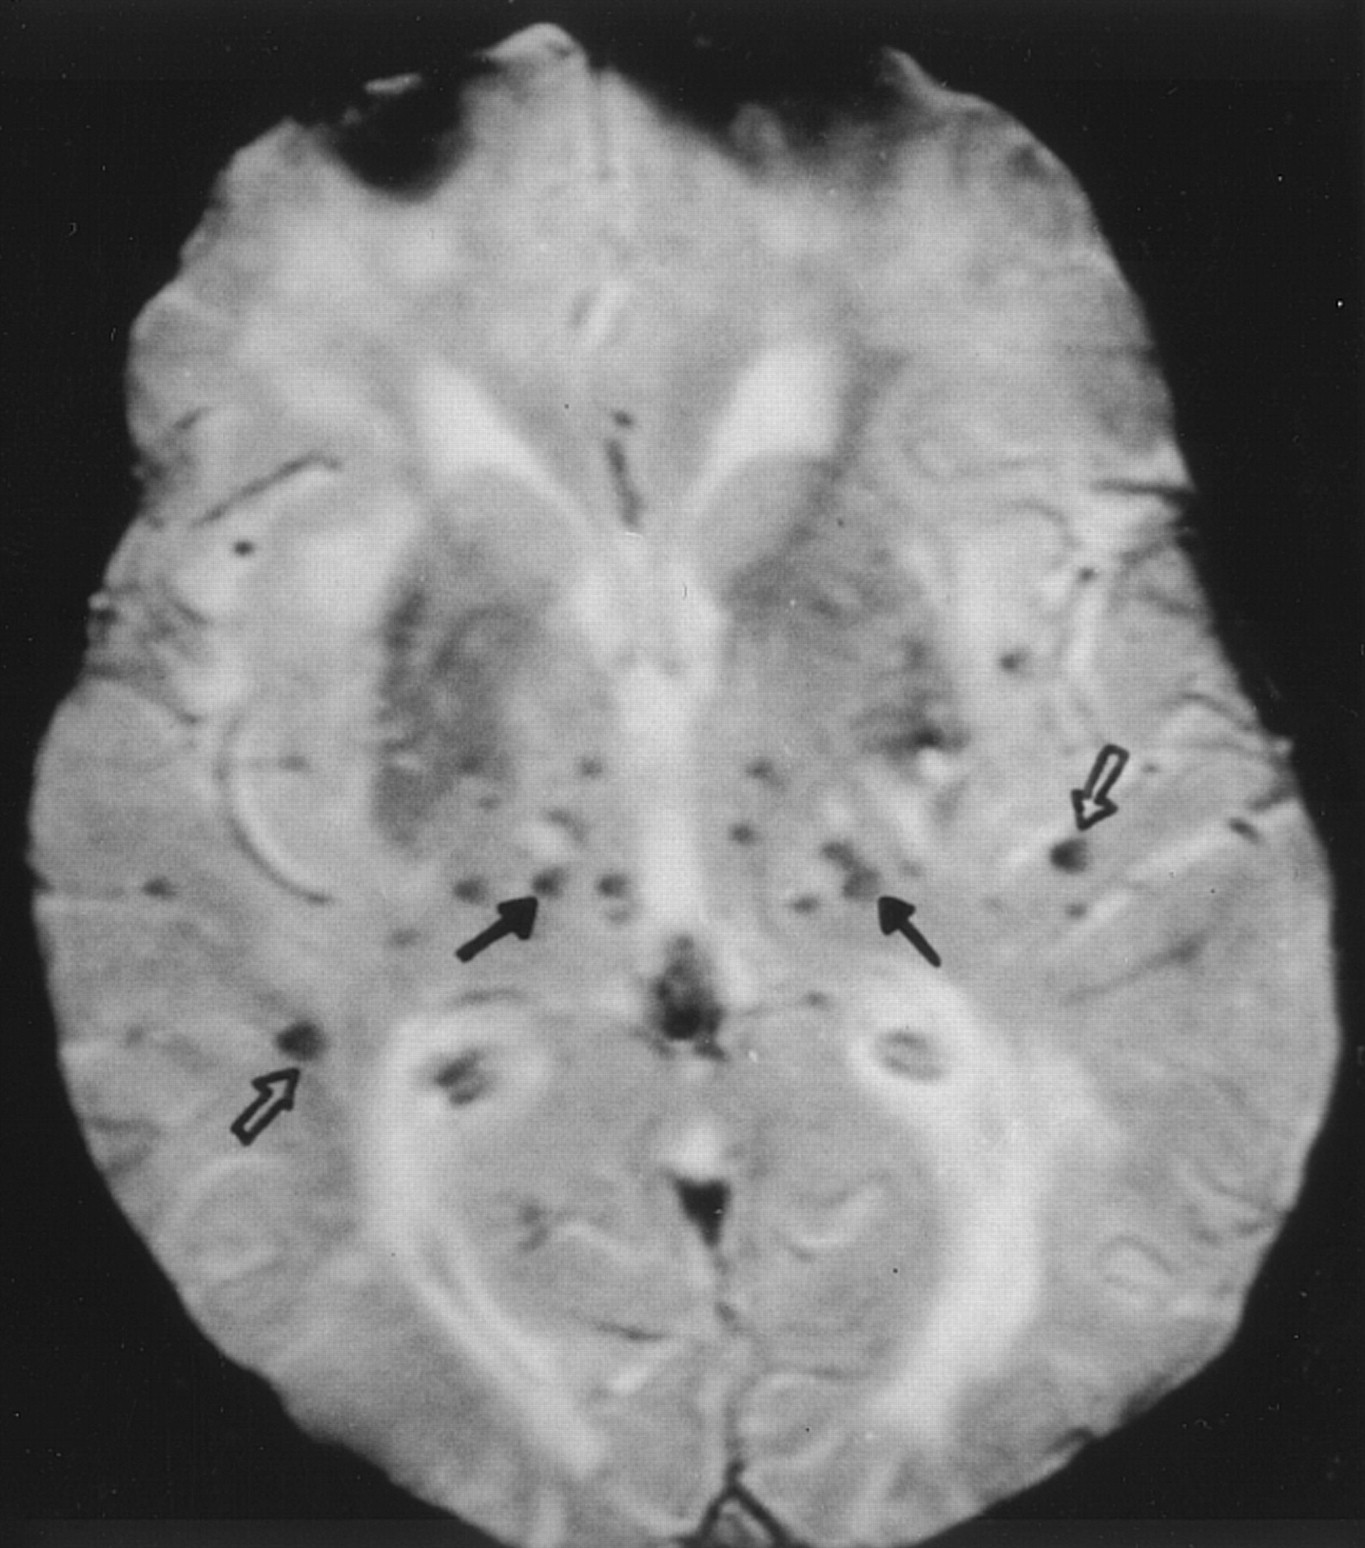

大脑在CADASIL microbleeds

Lesnik Oberstein et al。获得15个成员的t2加权MRI梯度回波荷兰CADASIL家庭确定脑microbleeds发生缺血性血管病变。Microbleeds CADASIL突变携带者症状出现在31%,暗示可能颅内出血的风险增加。